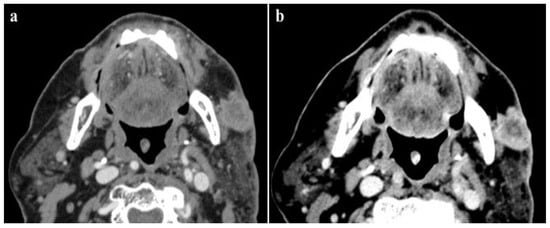

This evidence offers the possibility to reduce the amount of CM administered by 50% while maintaining the same diagnostic performance as the SECT acquisition with the standard amount of CM (Figure 5).

Figure 5.

A 95-year-old male patient with low glomerular filtrate rate (GFR 30 mL/min), submitted to a DECT examination for loco-regional neoplasm staging after the injection of 60 mL of contrast medium. The detection of the lesion, as well as the evaluation and definition of skin infiltration of this enhancing tumor, were better evaluated by the low-energy image (40 keV) (a) when compared to the corresponding polychromatic image (b), with a consistently reduced amount of contrast agent.